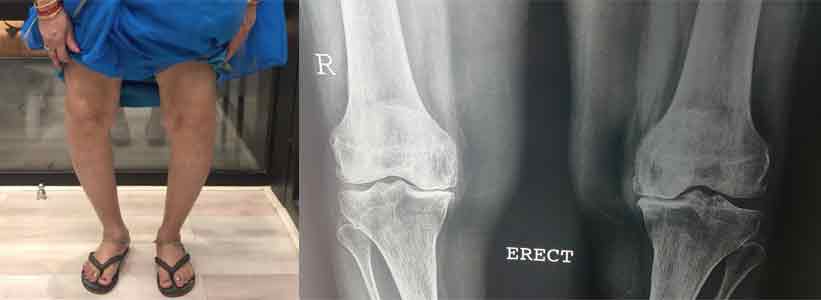

Varus Deformity

Before Surgery